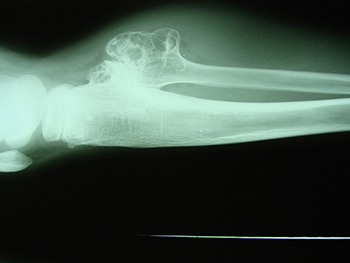

Osteocondroma

Tumor ósseo de origem cartilaginosa mais comum, com características benignas, porém com potencial de malignização.